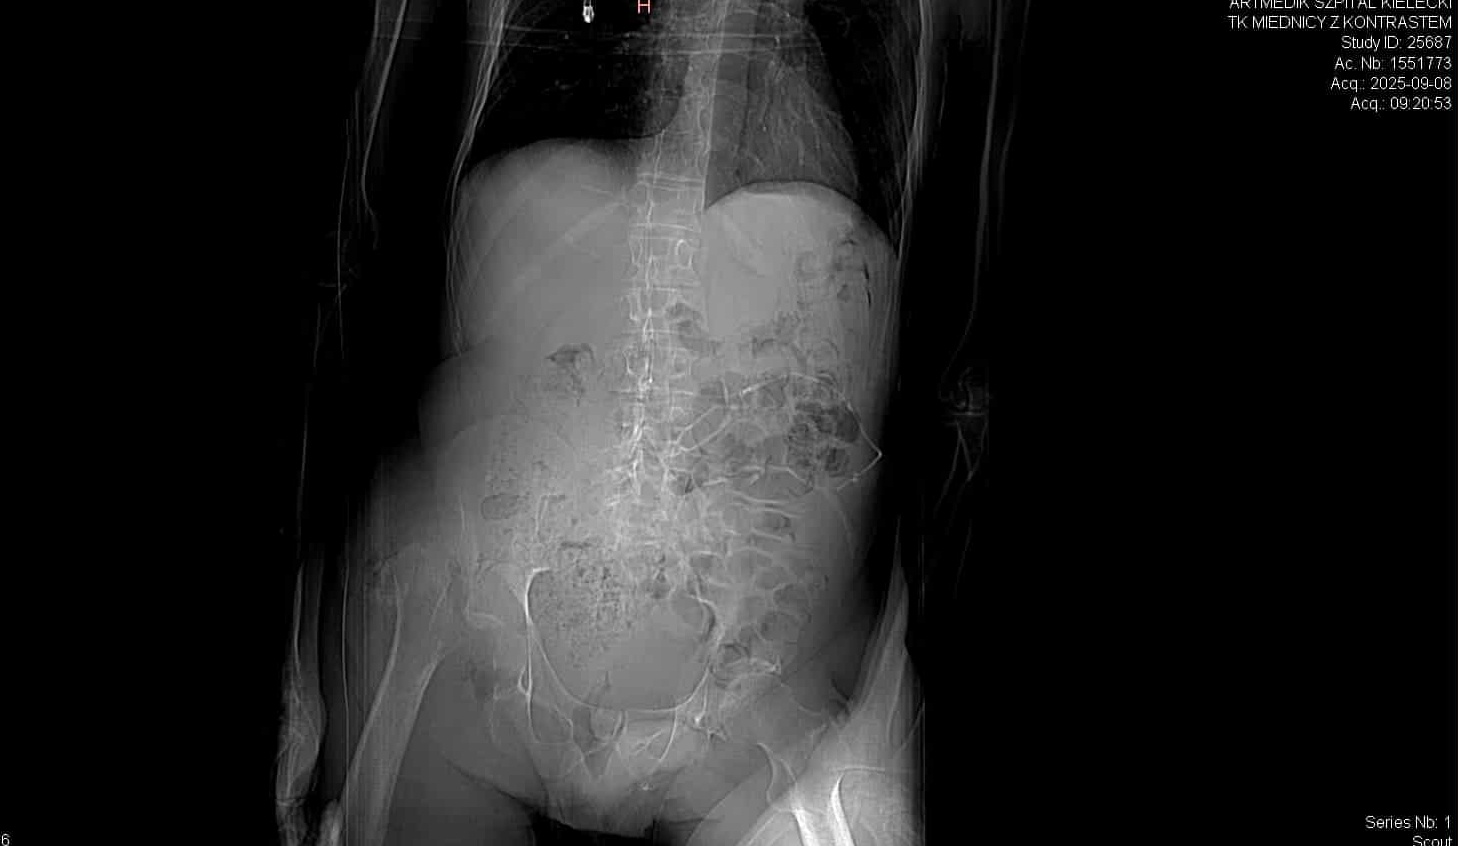

badanie: